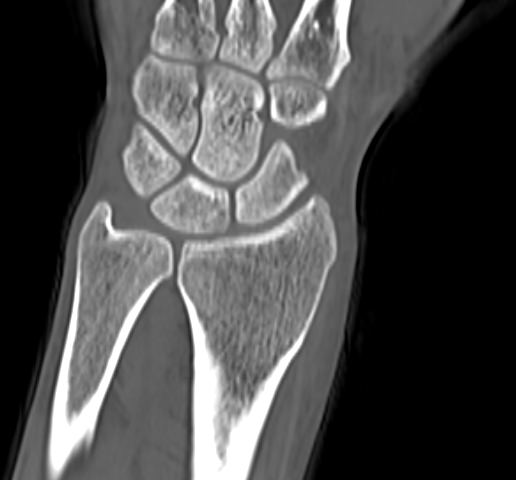

В компьютерном томографе излучатель рентгеновских лучей установлен в кольцевой части аппарата и, непрерывно вращаясь вокруг зоны исследования, производит послойное сканирование в различных плоскостях. В результате получаются снимки сустава в мельчайших подробностях, а после цифровой обработки полученных данных – точные трехмерные объемные модели исследуемой области. При этом изображения сустава можно приблизить, повернуть в разные стороны, что значительно повышает точность диагностики заболеваний костно-суставного аппарата.

Мультиспиральная КТ одного сустава наиболее часто применяется в ортопедии, травматологии, хирургии, онкологии и ревматологии. Данное исследование позволяет диагностировать:

- Травматические повреждения костей скелета (различные переломы, ушибы надкостницы, вывихи, разрывы связок);

- Дегенеративно-дистрофические заболевания суставов (артрозы);